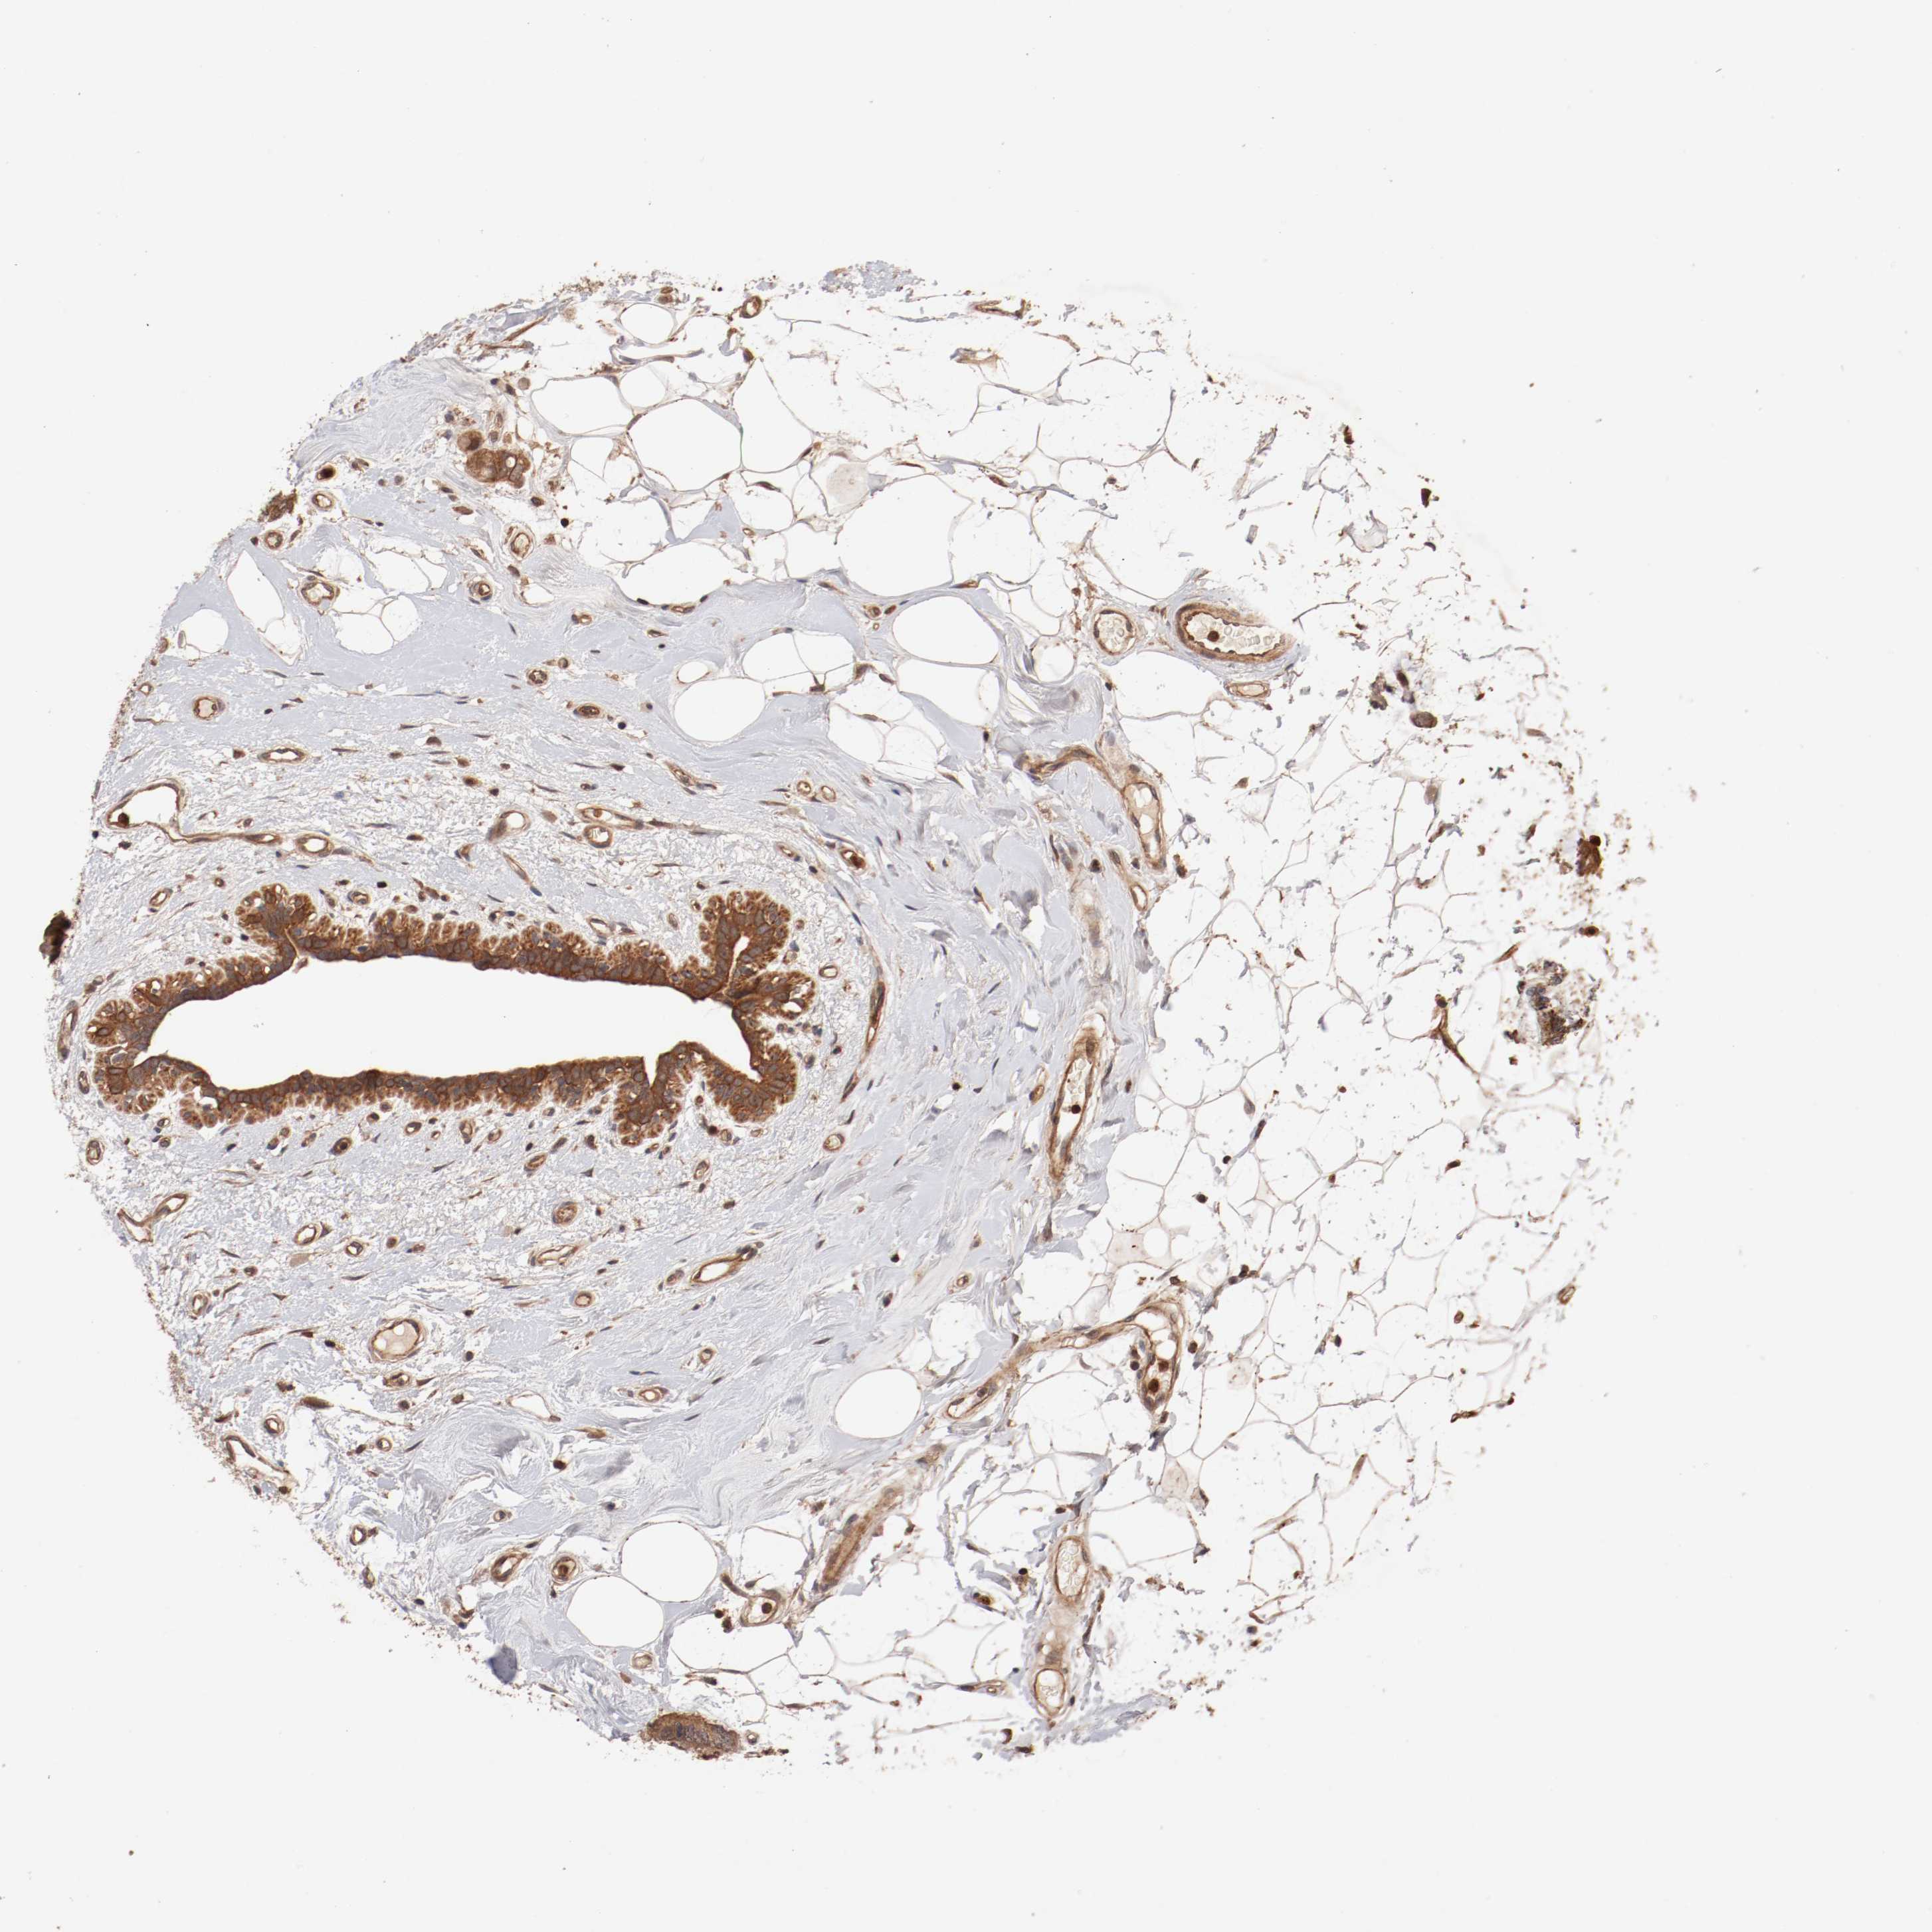

CANCER BREAST CANCER Show tissue menu

BRCA TCGA BRCA VALIDATION PROTEIN EXPRESSION